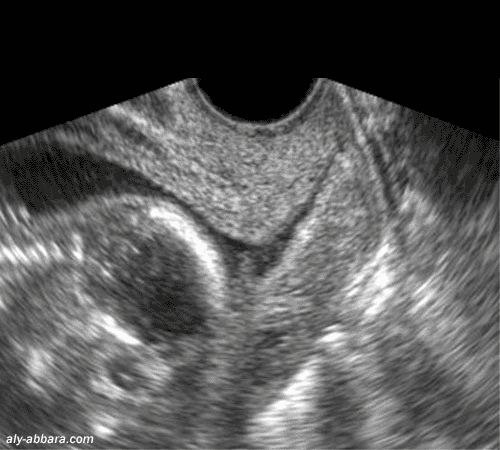

Coupe sagittale passant par le col utérin à 15 semaines d'aménorrhée

Il s'agit d'un col court (25 mm de longueur) avec orifice interne béant, sous forme d'un entonnoir

Incompétence cervico-isthmique (béance de l'orifice interne du col utérin)